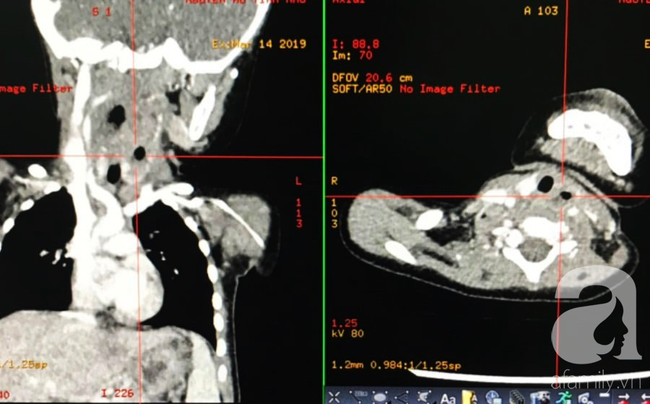

Hình ảnh X-quang và CT -Scan của các ổ áp-xe thành sau họng.

Tiến hành xét nghiệm máu khẩn và chụp CT-scan vùng cổ, kíp trực phát hiện bệnh nhân bị nhiễm trùng nặng, có nhiều ổ áp-xe tụ mủ chiếm hơn 2/3 thể tích của vùng cổ.

Ổ áp-xe sinh hơi làm dày khoang thành sau họng.

Quan sát trên hình CT-scan, khối u lan xuống khoang cổ sâu bên trái và nhiều cơ quan nguy hiểm.